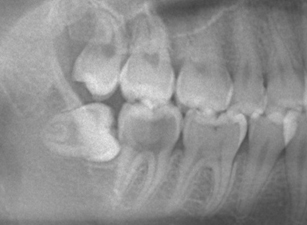

親知らずは「智歯」や「第三大臼歯」とも呼ばれ、お口の中の一番奥に生えてくる永久歯です。永久歯の中で最後に生えてくる歯であるため、生えてくるスペースが足りず横向きや斜めに傾いて生えたり、顎骨の中に埋まったまま生えてこないといった場合(埋伏智歯)もあります。

そうした親知らずは、歯肉の炎症を引き起こす原因になったり、隣の第二大臼歯の虫歯リスクを高める原因にもなり、歯並びに悪影響を及ぼすケースもあるため、精査したうえで抜歯をおすすめする場合があります。

当院では、抜歯前にレントゲン写真にて親知らずと神経との位置関係を確認し、十分精査したうえで診断を行っております。